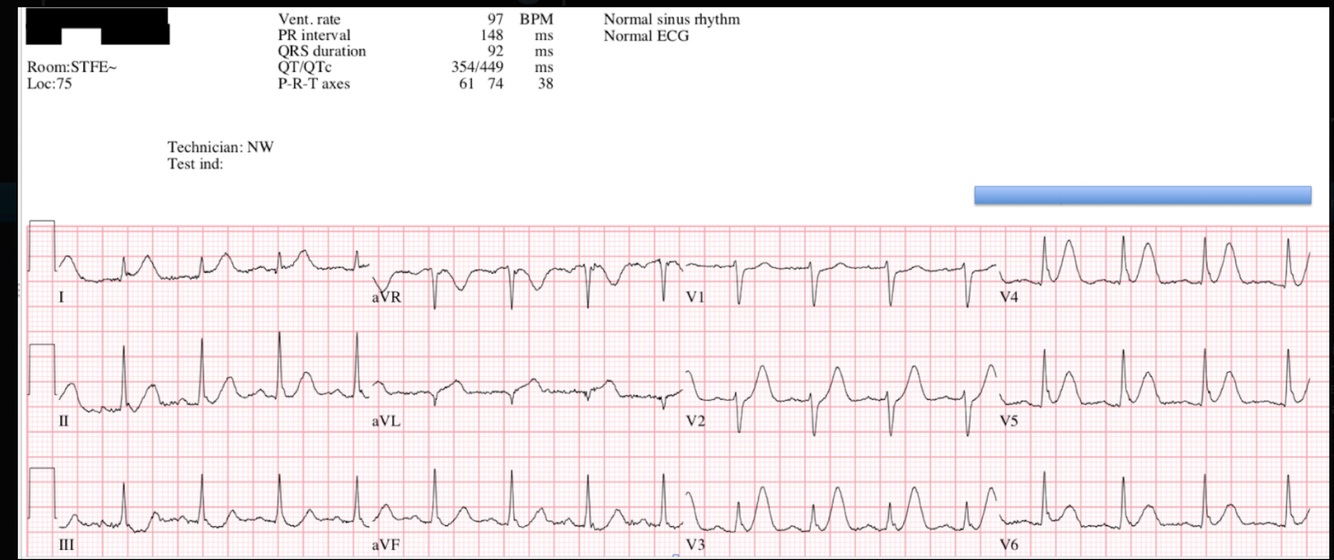

Hyperacute T-waves - Inferior 2

Broad, asymmetrically peaked or ‘hyperacute’ T-waves seen in early stages of MI.

Disproportionately increased area under the ST segment and T wave compared to the QRS

“Inflating the T-wave like a balloon”